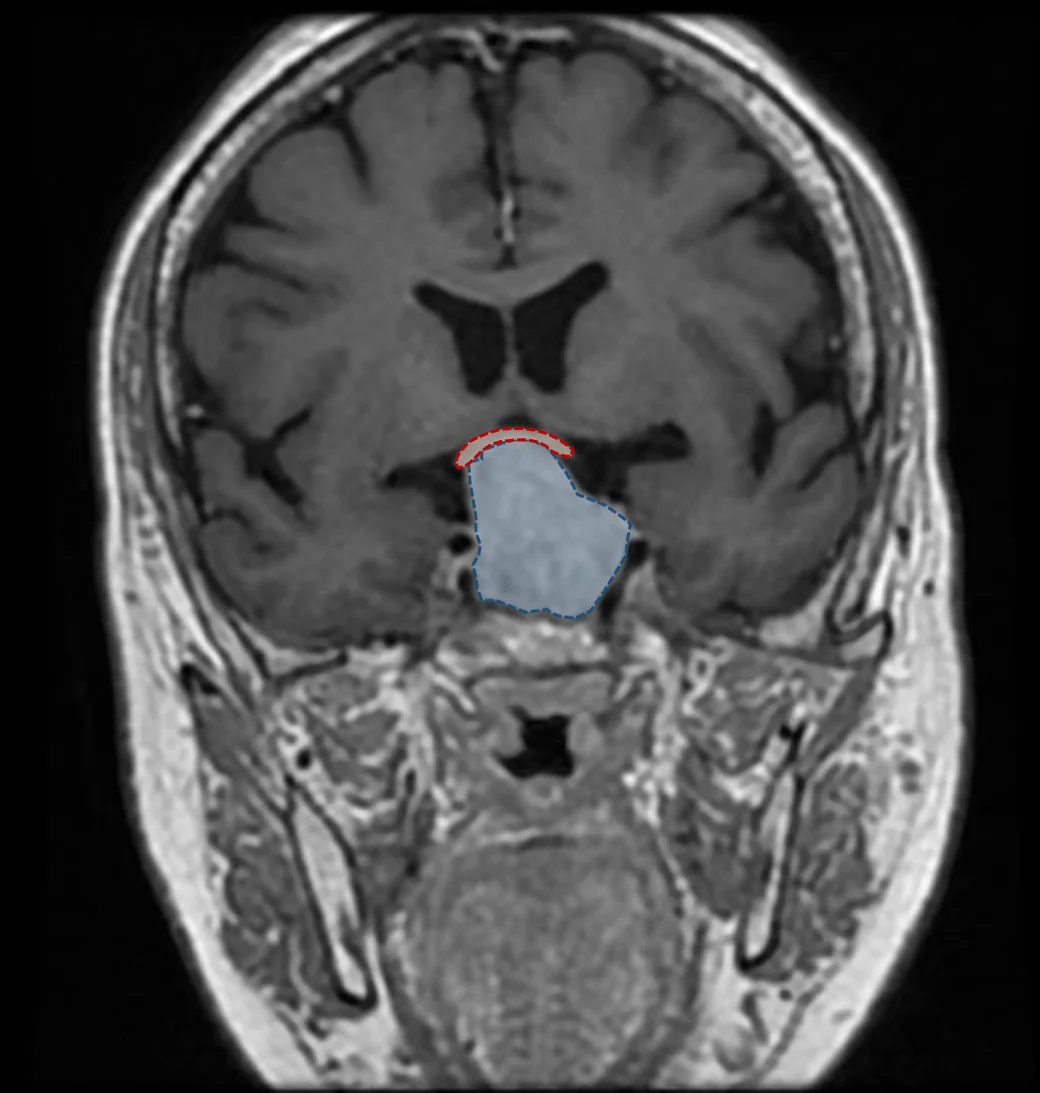

Le diagnostic d’adénome hypophysaire repose sur deux éléments que sont l’imagerie médicale et le bilan endocrinien. L’examen de référence à réaliser dans la recherche d’un adénome est une IRM cérébrale, qui permettra d’en évaluer la taille et le retentissement sur les structures adjacentes, notamment les voies visuelles. Les adénomes sont habituellement classés en deux groupes: les micro-adénomes (de moins de 10 mm de diamètre) et les macro-adénomes (de plus de 10 mm de diamètre). Le bilan endocrinien va quant à lui permettre de déterminer le niveau de sécrétion des différentes hormones sécrétées par l’hypophyse ainsi que leur retentissement sur l’organisme.

De par leur position à la base du cerveau, au sein de la selle turcique, une structure osseuse contenant l’hypophyse, les adénomes hypophysaires peuvent dans un grande majorité des cas être opérés sans ouvrir la boîte crânienne en passant par l’intérieur des fosses nasales. La chirurgie est habituellement courte (30 à 60 minutes), sans cicatrice visible, avec une hospitalisation en moyenne de 3 jours.